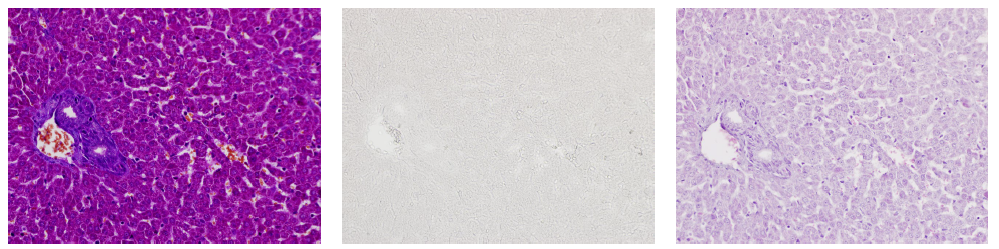

• 使用小(xiǎo)鼠腦(nǎo)(海馬)标本進行(xíng)HE染色時(shí)

• 使用deColorizing Solution 1進行(xíng)脫色

HE染色

脫色

抗體(tǐ)染色

紅色:Iba1,藍(lán)色:DAPI

• 使用小(xiǎo)鼠肝髒标本進行(xíng)MT染色時(shí)

• 使用deColorizing Solution 1和(hé)2進行(xíng)脫色

左至右:MT染色→脫色→HE染色

(數(shù)據提供:麻布大(dà)學小(xiǎo)澤秋沙先生(shēng)、坂上(shàng)元榮先生(shēng))